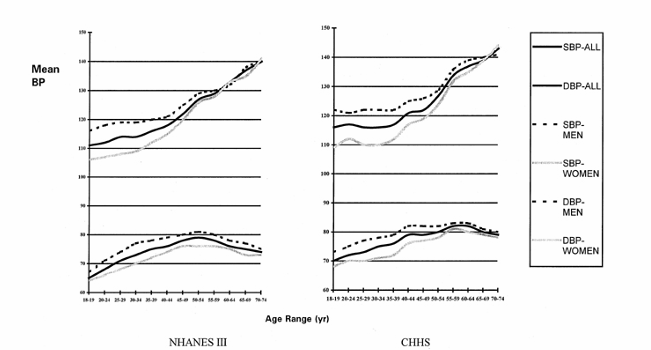

consequences of uncontrolled hypertension